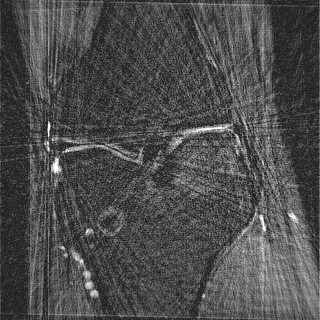

This article presents a novel undersampled magnetic resonance imaging (MRI) technique that leverages the concept of Neural Radiance Field (NeRF). With radial undersampling, the corresponding imaging problem can be reformulated into an image modeling task from sparse-view rendered data; therefore, a high dimensional MR image is obtainable from undersampled $k$-space data by taking advantage of implicit neural representation. A multi-layer perceptron, which is designed to output an image intensity from a spatial coordinate, learns the MR physics-driven rendering relation between given measurement data and desired image. Effective undersampling strategies for high-quality neural representation are investigated. The proposed method serves two benefits: (i) The learning is based fully on single undersampled $k$-space data, not a bunch of measured data and target image sets. It can be used potentially for diagnostic MR imaging, such as fetal MRI, where data acquisition is relatively rare or limited against diversity of clinical images while undersampled reconstruction is highly demanded. (ii) A reconstructed MR image is a scan-specific representation highly adaptive to the given $k$-space measurement. Numerous experiments validate the feasibility and capability of the proposed approach.